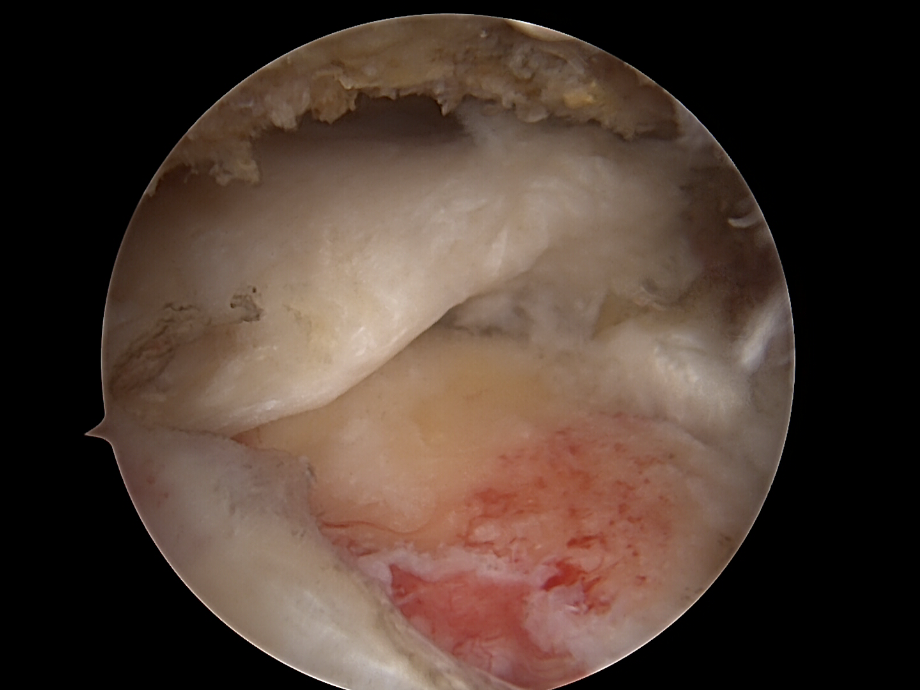

Arthroskopische Diagnostik

• Einführung der Arthroskopkamera über den hinteren (posterioren) Zugang).

• Inspektion des Glenohumeralgelenks und des Subakromialraums.

• Beurteilung der Rupturform: partiell, vollständig, zurückgezogen, degenerativ, traumatisch.

rotatorenmanschette von dr. timmel von ortho-timmel.at

Darstellung und Mobilisierung der Sehnenstümpfe

• Débridement von degeneriertem Gewebe.

• Mobilisierung der rupturierten Sehne (meist Supraspinatus, ggf. Infraspinatus/Subscapularis).

• Darstellung des Ansatzbereichs am Knochen (Tuberculum majus/minus humeri).

• Glättung und Anfrischen des Footprints (Sehnenansatzstelle) zur Förderung der Knochen-Sehnen-Heilung.